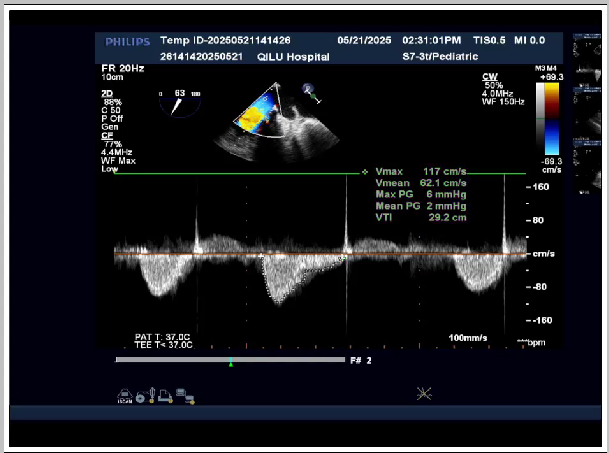

第一次高压球囊扩后超声:平均压差:3mmHg 峰值压差:9mmHg

第二次高压球囊扩后超声:平均压差:2mmHg 峰值压差:6mmHg